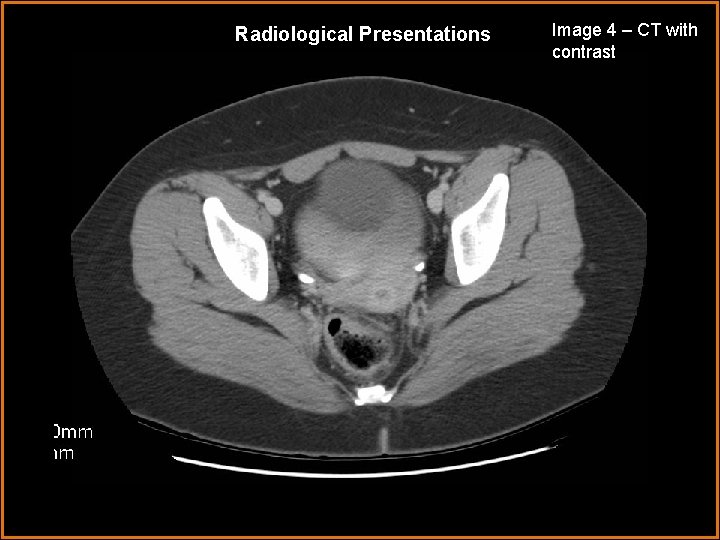

Radiological Presentations Image 4 – CT with contrast

Findings and Differentials Findings: Image 1 – Transabdominal ultrasound image showing a normal uterus with a large cystic mass separate and superior to the bladder. Image 2 – Color Doppler image of the right adnexa showing some color flow within an apparently enlarged but incompletely visualized right ovary. No spectral Doppler was performed. Image 3 – CT image of the pelvis showing an enlarged right ovary and a large cystic mass superior to the bladder. Image 4 – CT image inferior to image 3 confirms the cystic mass separate from and superior to the bladder. Differentials: • Ovarian torsion • Hemorrhagic ovarian cyst • Dermoid